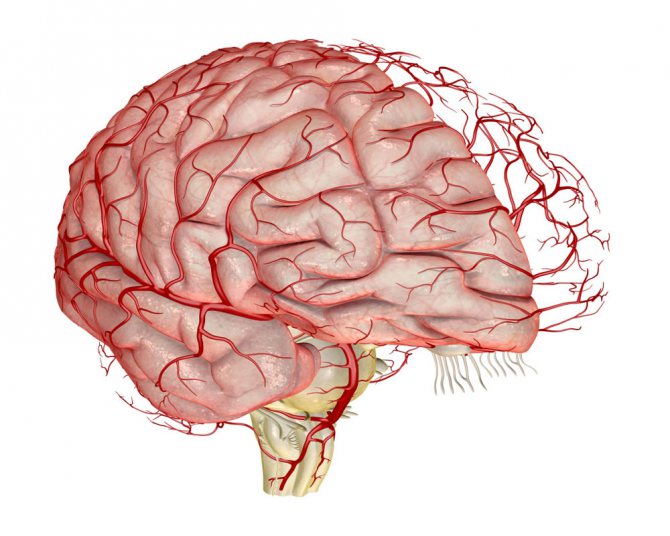

Венозная система мозга представляет собой сложный механизм, который поддерживает высокий уровень нервной активности. Она играет ключевую роль в жизненно важных физиологических процессах, обеспечивая постоянное поступление крови в главный орган центральной нервной системы. Дисциркуляция, или затрудненный венозный отток, свидетельствует о том, что нормальное кровообращение нарушено. Это может привести к дисбалансу кислорода, жиров, углеводов и воды в головном мозге.

Для подтверждения венозного застоя применяются современные инструментальные методы исследования:

- Компьютерная томография (КТ) или магнитно-резонансная томография (МРТ) головного мозга. Эти методы позволяют с высокой точностью визуализировать изменения в тканях и сосудах главного органа центральной нервной системы.

- Ангиография – инструментальный метод, который позволяет визуализировать сосуды головного мозга. Процедура помогает выявить участки сужения или закупорки сосудов, а также определить места и уровень их расширения, наличие кровотечений, опухолей и другие проблемы, которые невозможно диагностировать другими способами.